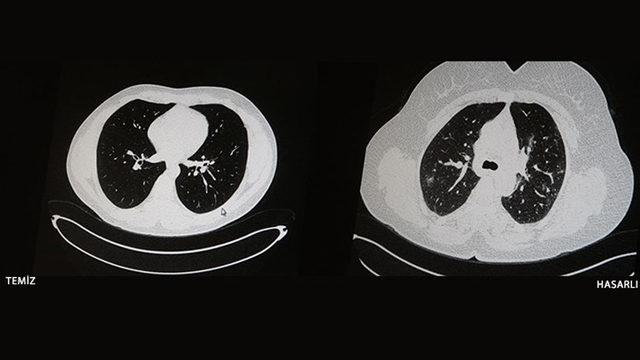

İçerikten Görseller